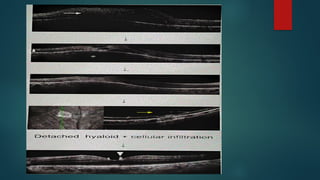

2. Inflammatory cellular infiltrate of

overlying vitreous:

 Granulomatous precipitates of

posterior hyaloid

 Dense vitreous opacities or

bands.

 Active lesions can induce vitreous

haze causing HEADLIGHT IN FOG

APPEARANCE